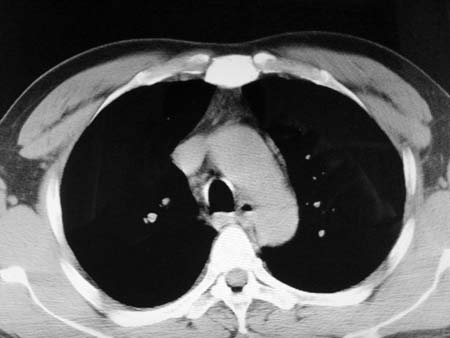

以下是引用qian在2008-4-27 17:02:00的发言:[br]考虑右下肺肺段隔离症伴有感染,建议做增强看看。

以下是引用zsl6918在2008-4-27 17:13:00的发言:[br]考虑右肺下叶炎性病变可能性大,建议抗炎治疗后复查,现有资料不能完全除外肺癌可能。